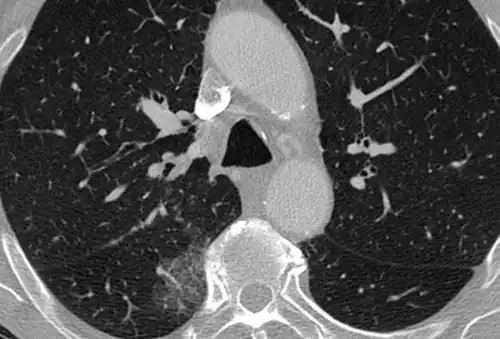

High-resolution CT image showing ground-glass opacities in the periphery of both lungs in a patient with COVID-19 (red arrows). The adjacent normal lung tissue with lower attenuation appears as darker areas.

Ground-glass opacity is among the most common imaging findings in patients with confirmed COVID-19.[16][17] One systematic review found that among patients with COVID-19 and abnormal lung findings on CT, greater than 80% had GGOs, with greater than 50% having mixed GGOs and consolidation.[16] GGOs with mixed consolidation has most often been found in elderly populations.[18] Several studies have described a pattern among initial, intermediate, and hospital discharge imaging findings in the disease course of COVID-19. Most commonly, initial CT imaging reveals bilateral GGOs at the periphery of the lungs. During initial stages, this is most often found in the lower lobes, although involvement of the upper lobes and right middle lobe has also been reported early in the disease course.[16][18] This is in contrast to the two similar coronaviruses, SARS and MERS, which more commonly involve only one lung on initial imaging.[19][20] As the COVID-19 infection progresses, GGOs typically become more diffuse and often progress to consolidation.[11][18] This is sometimes accompanied by the development of a crazy paving pattern and interlobular septal thickening.[18] In many cases the most severe pulmonary CT abnormalities occurred within 2 weeks after symptoms began.[17] At this point, many individuals begin showing resolution of consolidation and GGOs as symptoms improve. However, some patients have worsening symptoms and imaging findings, with further increase in septal thickening, GGOs, and consolidation. These patients may develop lung "white-out" with progression to acute respiratory distress syndrome (ARDS) requiring treatment escalation.[17][21]